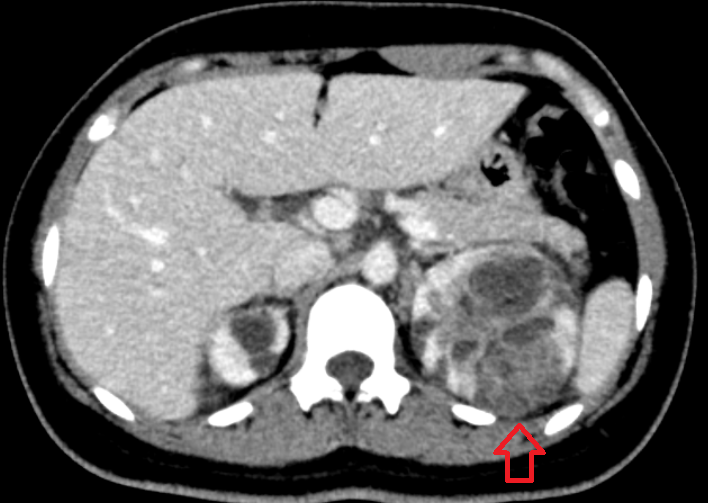

발열 복통으로 오셔서 게실염이 발견된 사례